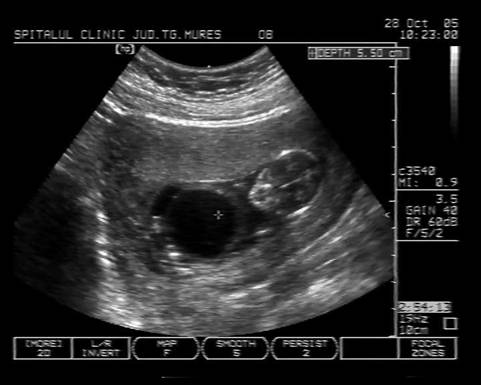

Fig. nr.128 Pliu nuchal cu dimensiunea de 2,9 mm.Cu sageata se remarca alaturat amniosul, magnificatia redusa nu permite obtinerea unei imagini optimale a translucentei nuchale.

Fig. nr.129 Masurarea pliului nuchal la o marire corespunzatoare

Masurarea NT egala sau peste 3 mm este considerata anormala. Riscul defectelor cromozomiale creste marcat in functie de marimea NT si de varsta mamei, necesitand punctie biopsie de vilozitati choriale sau amniocenteza.

Cea mai buna metoda de screening [18] ramane asocierea varstei materne, masurarea translucentei nuchale si nivelul seric matern de HCG β- human chorionic gonadotropin si PAPP-A (Pregnancy associated plasma protein- A) la 11 - 14 sapt gestationale ( dublu test ). Detectarea defectelor cromozomiale este in jur de 90%, cu ajutorul unui soft ce integreaza aceste date si efectueaza calculul riscului relativ.